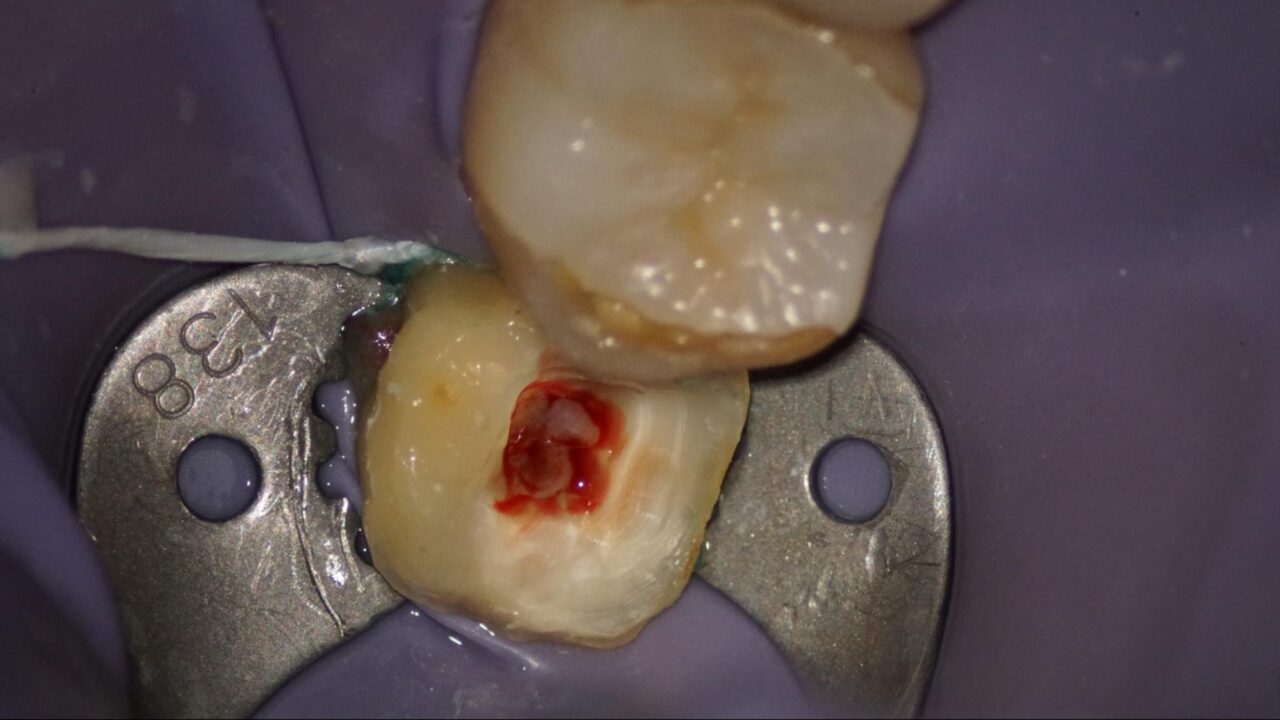

症例1:歯の中の神経が出血して歯髄炎を起こしているケース

歯の中の神経、歯髄が充血しています。

歯髄の状態が出血をしている場合、歯髄炎を起こしている事が多くあります。